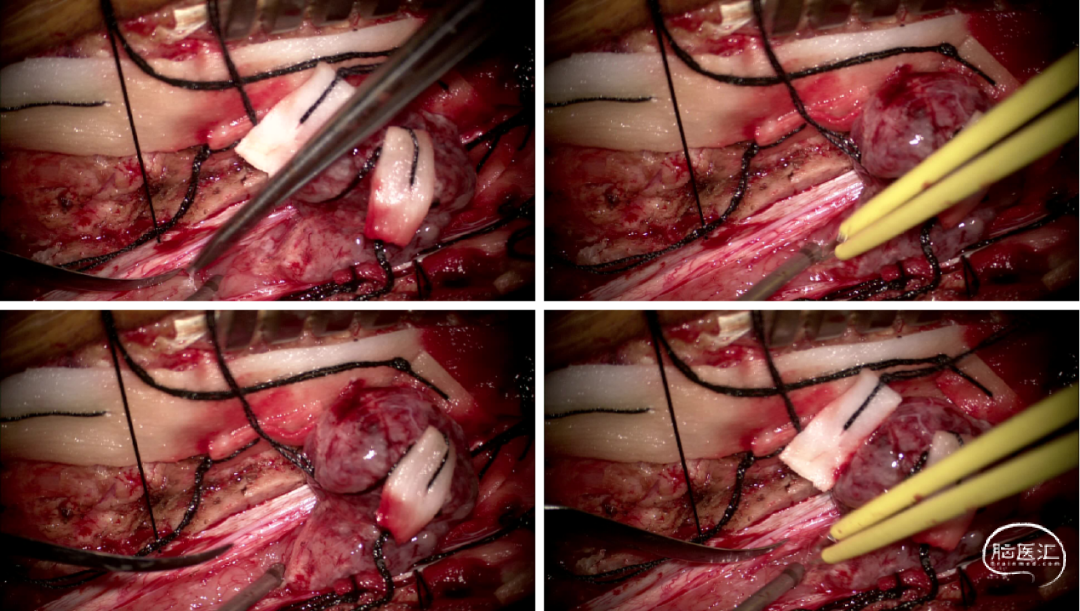

手术情况

硬脊膜张力高,脊髓向背侧膨出,与脊髓腹侧粘连紧密,肿瘤挤压脊髓,肿瘤边界分离,减少对胸髓的牵拉,降低了术后患者神经功能发生的概率,术后患者肢体麻木症状改善。